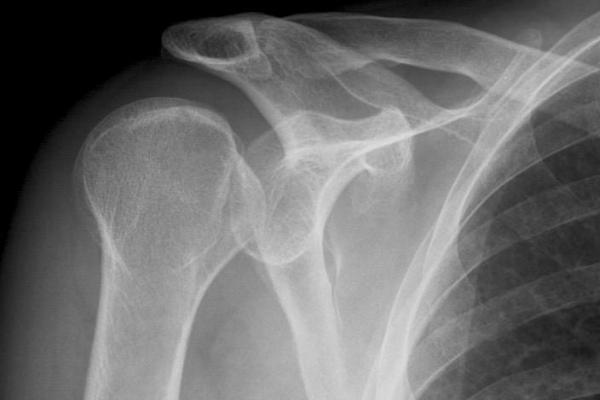

Artropatia gleno-omerale: classificazione - Trattamento conservativo nelle patologie degenerative - Le protesi di spalla

Le complicanze chirurgiche e riabilitative - Osservazione e valutazione clinica del paziente - Valutazione e trattamento delle discinesie scapolari (nuovi concetti) Presentazione casi clinici, valutazione dei pazienti - Discussione sui casi clinici analizzati - Il trattamento chirurgico - Esercizi specifici di rinforzo

Le complicanze chirurgiche e riabilitative - Osservazione e valutazione clinica del paziente - Valutazione e trattamento delle discinesie scapolari (nuovi concetti) Presentazione casi clinici, valutazione dei pazienti - Discussione sui casi clinici analizzati - Il trattamento chirurgico - Esercizi specifici di rinforzo Le schede di valutazione - Il recupero della mobilità articolare passiva ed attiva - Parte pratica: Mobilizzazioni passive e tecniche di presa - Valutazione Clinica/funzionale